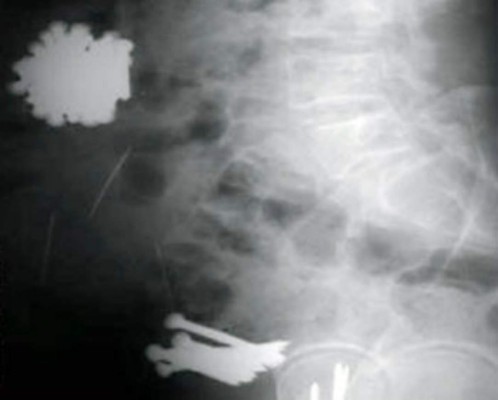

Una mujer israelí se tragó una cucaracha y luego el tenedor con el que intentaba sacársela de la garganta, según muestra esta radiografía. El cirujano removió el tenedor con una laparoscopia, una cirugía poco invasiva en el abdomen de un paciente.

La mujer se recuperó satisfactoriamente. 04/12/2019 - 00:005 / 10 -